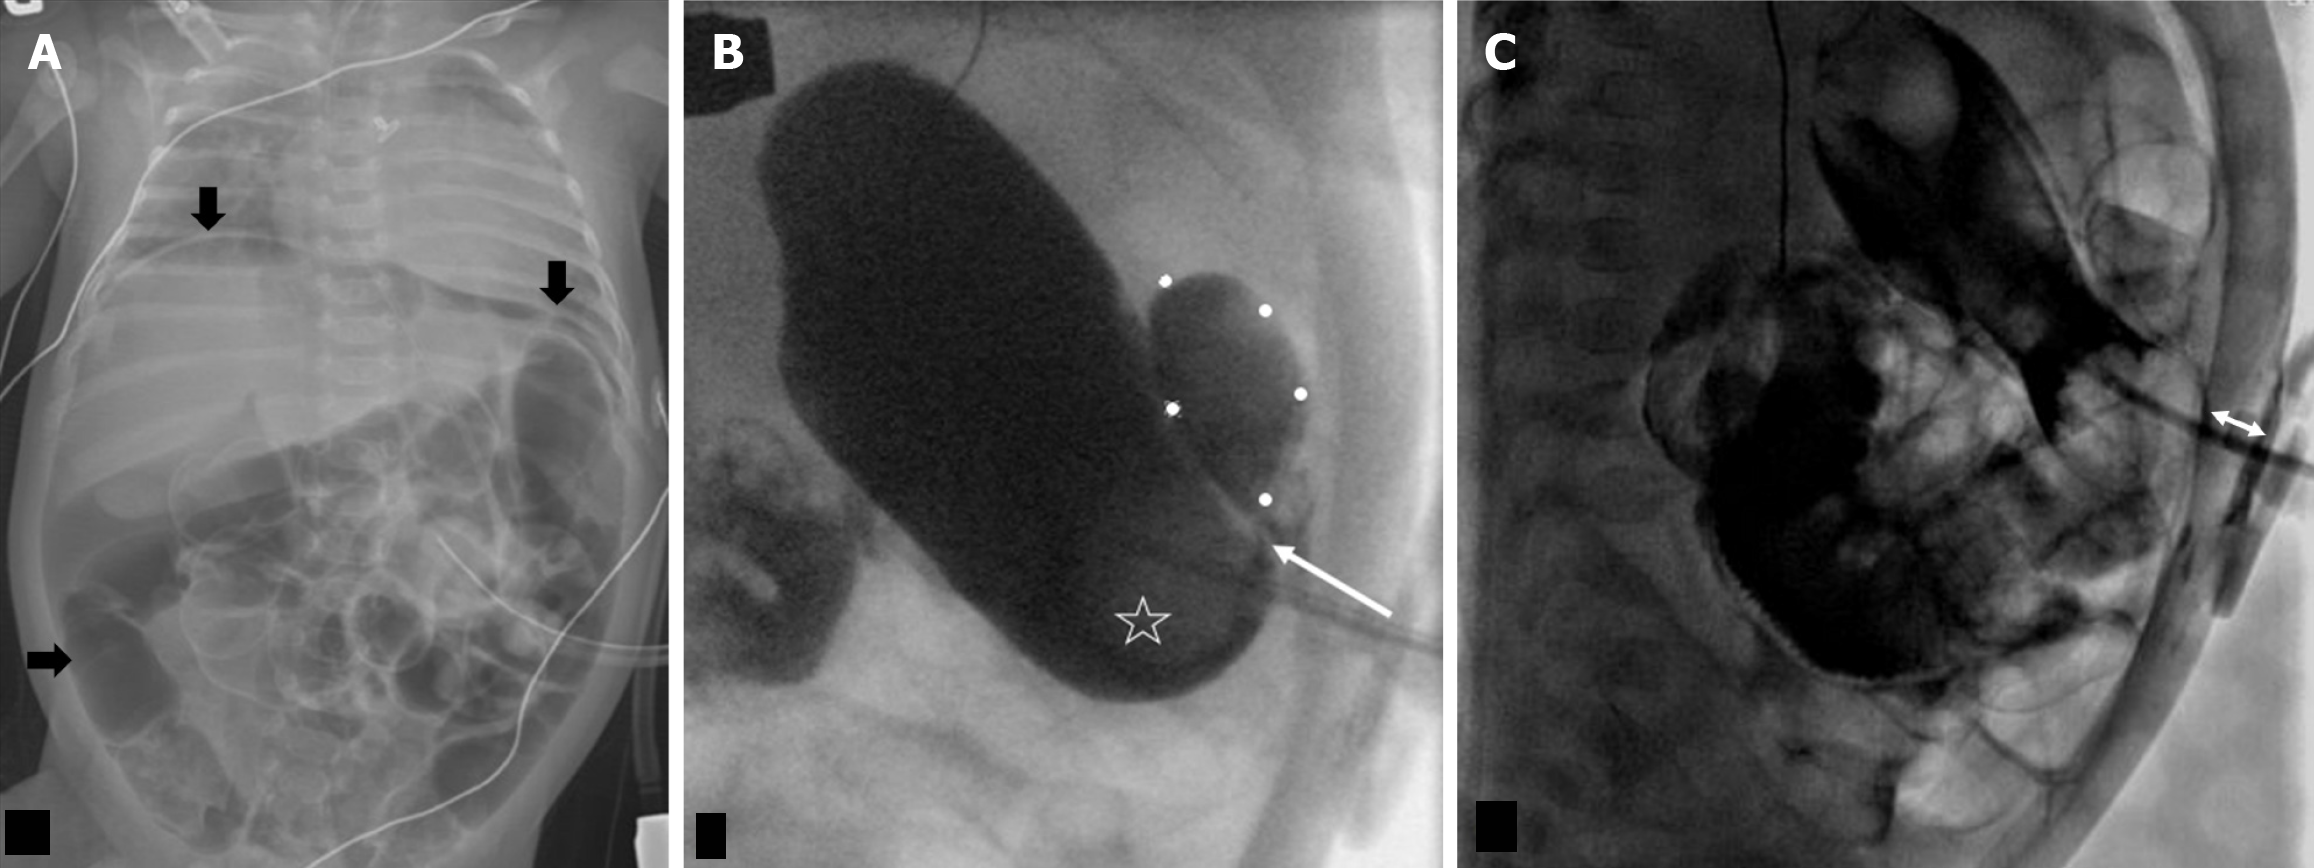

Figure 4 Intraperitoneal leak via the gastrostomy tube tract, 2 month old postoperative day 1 open gastrostomy tube placement.

A: Frontal abdominal radiograph with a large amount of pneumoperitoneum (black arrows); B: Frontal projection in a fluoroscopy gastrostomy tube (G-tube) study with a loculated intraperitoneal leak (outlined by white dotes). There is transit of contrast behind the G-tube ballon (star) into the peritoneal leak (arrow); C: G-tube was exchanged in interventional radiology, following which a lateral fluoroscopic image showed the narrowed distance (double arrow) between the disc and ballon with no trickling of contrast behind it.